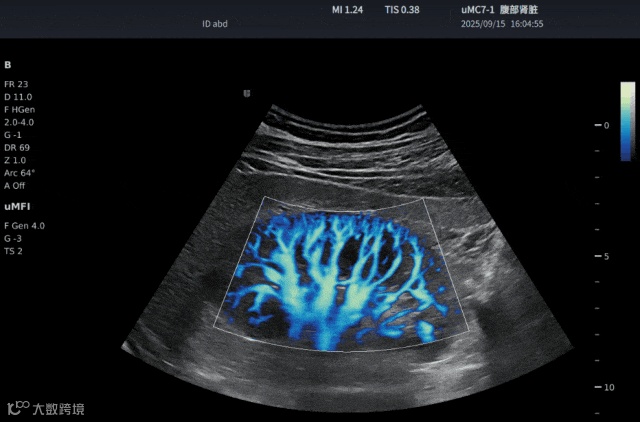

SensiFlow 超敏血流技术

能够捕捉直径不足百微米的微血管血流信号,实现类造影效果的微循环成像。相较市售设备仅能分辨肾脏三级血管,SensiFlow可显示至四级血管血流。对于肠管、胆囊息肉、肿瘤新生血管等以往难以显像的细微结构,也能稳定呈现。